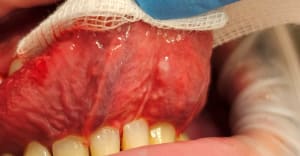

20-04-2021 Panoramique Début.JPG